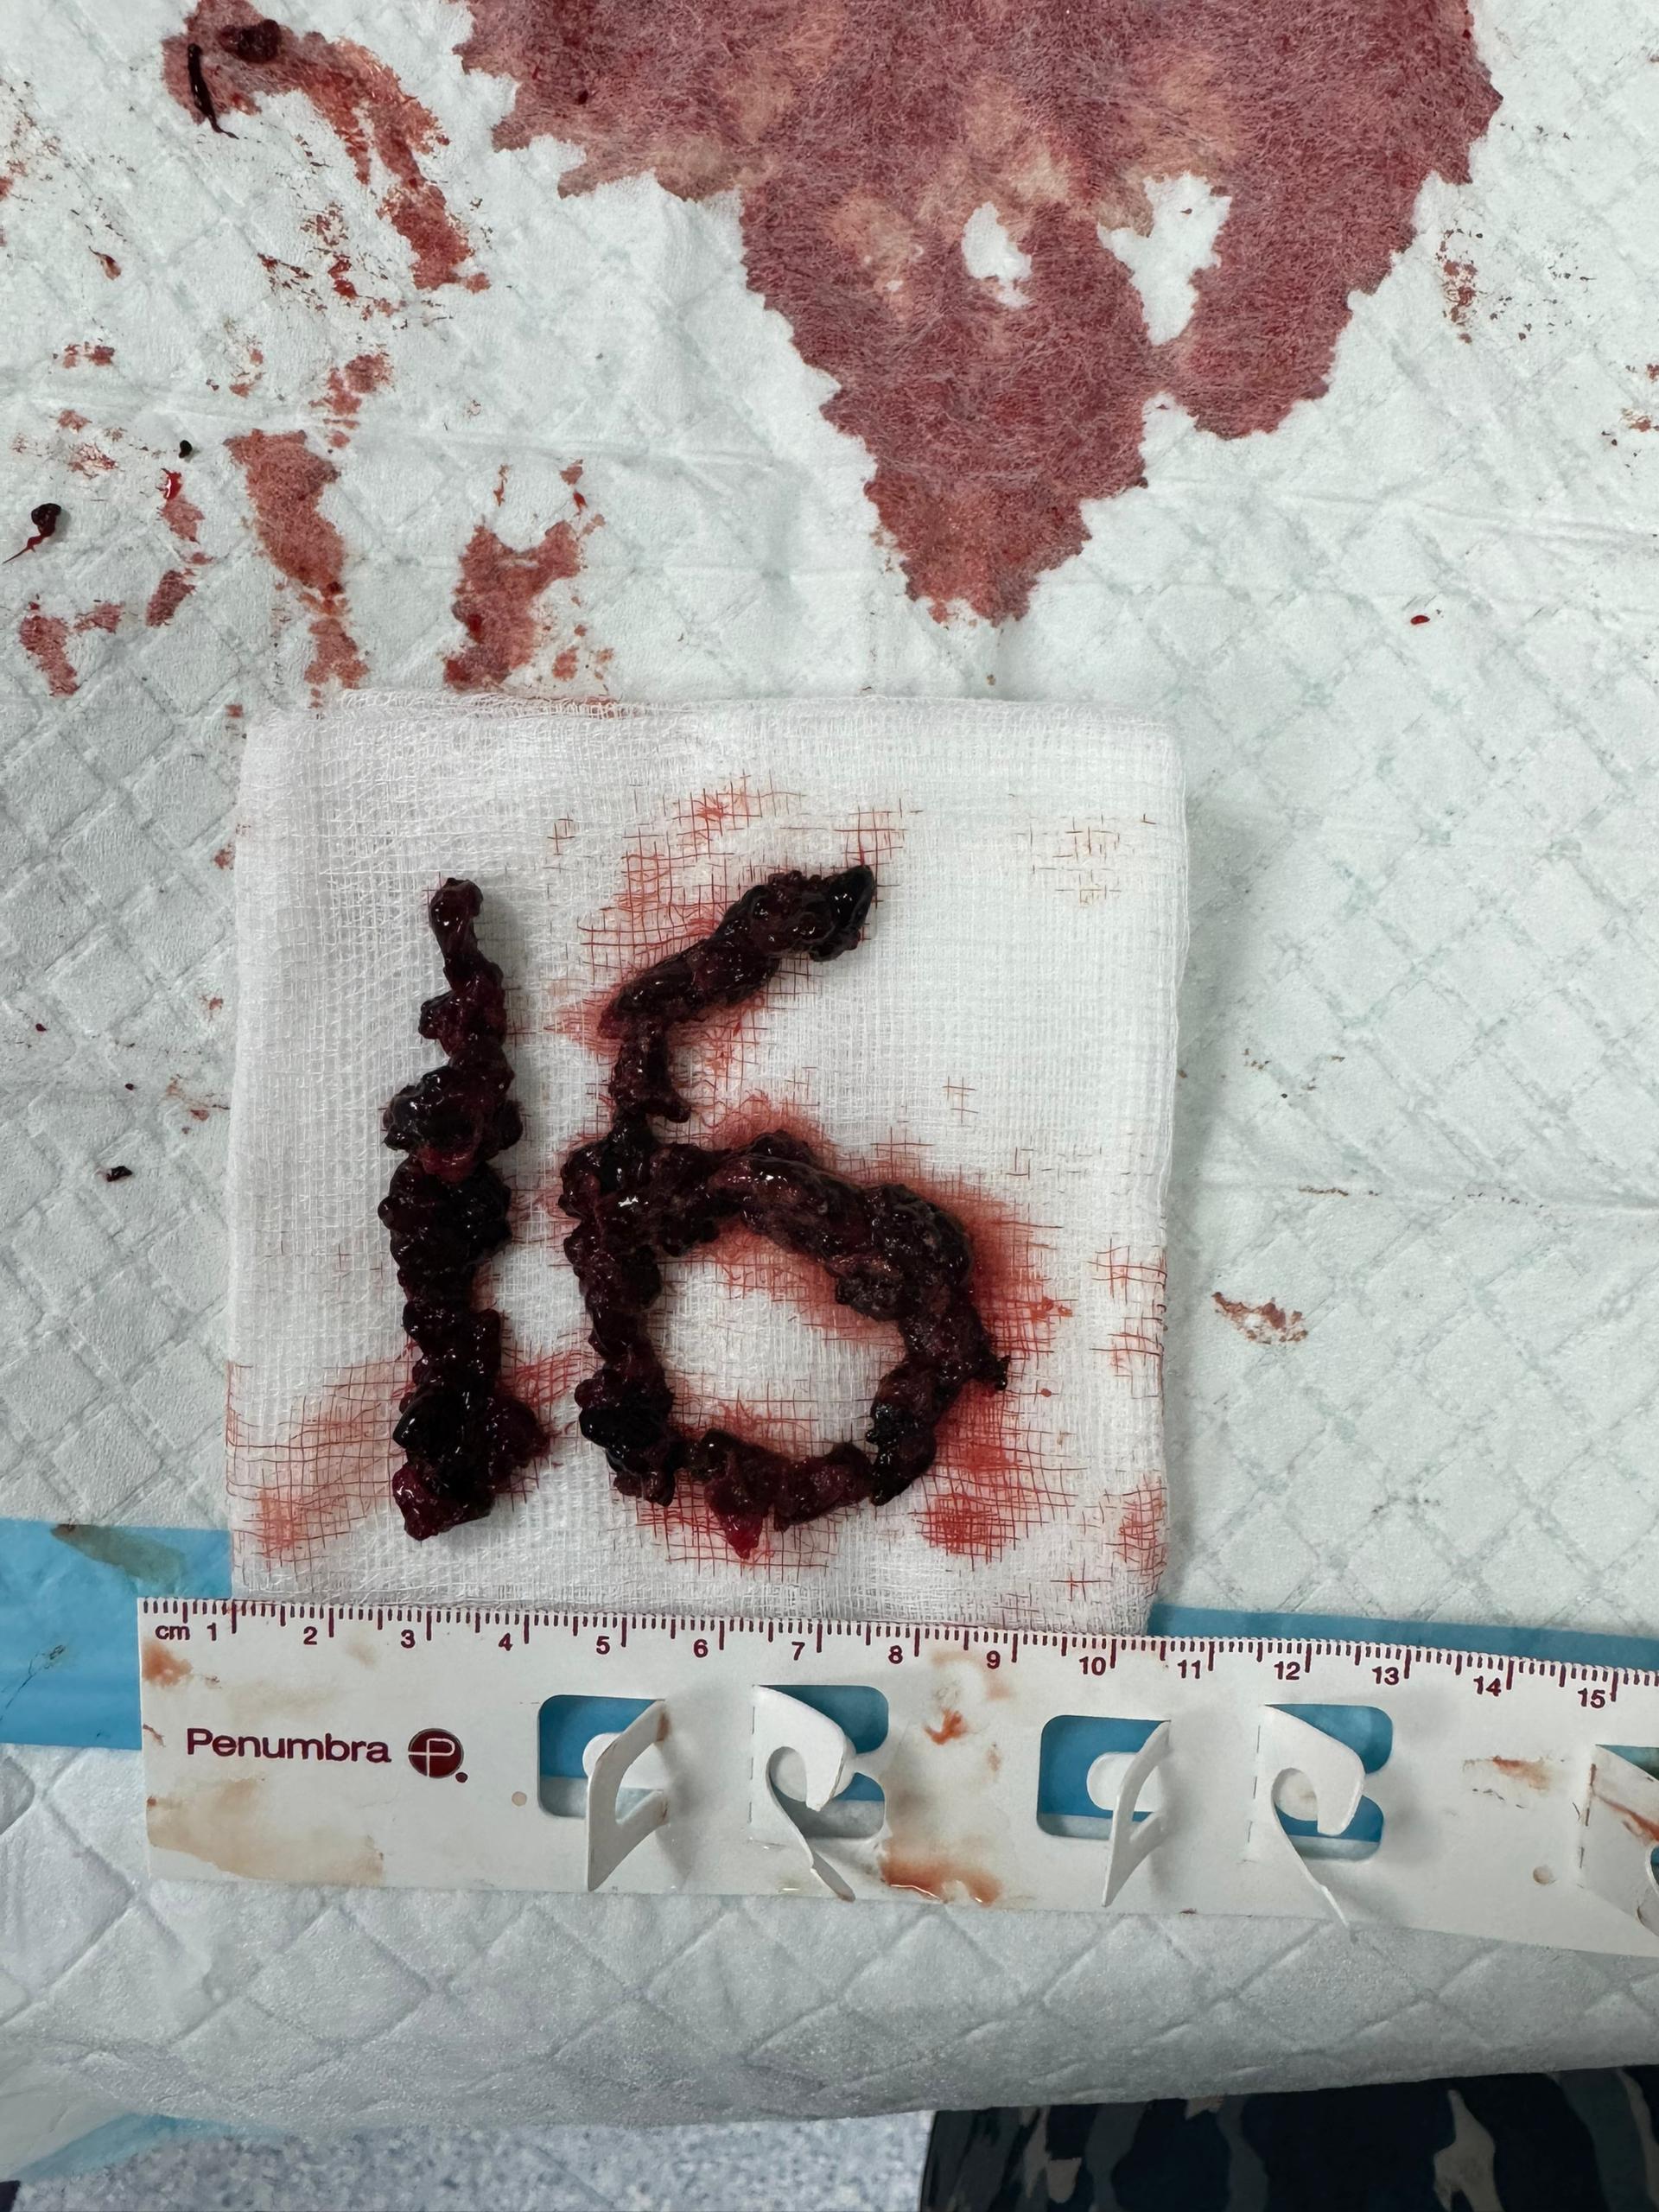

Right femoral vein access was obtained under ultrasound and fluoroscopy guidance. A 6Fr multipurpose (MP) catheter was used to deliver a J-tip guidewire into the main pulmonary artery, which was then exchanged for a pigtail catheter. Digital subtraction angiography revealed filling defects in the truncus anterior and bilateral interlobar arteries. The 6Fr femoral sheath was upsized to a 16Fr sheath. The Penumbra ENGINE and Lightning Flash 2.0 system, with a 16Fr aspiration catheter, was primed. Using the MP catheter, the J-tip guidewire was delivered into the left pulmonary artery and exchanged for the 16Fr aspiration catheter. Multiple aspiration runs were performed using the computer-assisted vacuum thrombectomy system. The same steps were repeated for the right pulmonary artery. The procedure lasted 2 hours, with 1.2L of blood loss and approximately 6-8 cubic centimeters of fresh clots aspirated. The patient received 2 units of packed red blood cells during the procedure. Femoral access was closed with a figure-of-8 suture.